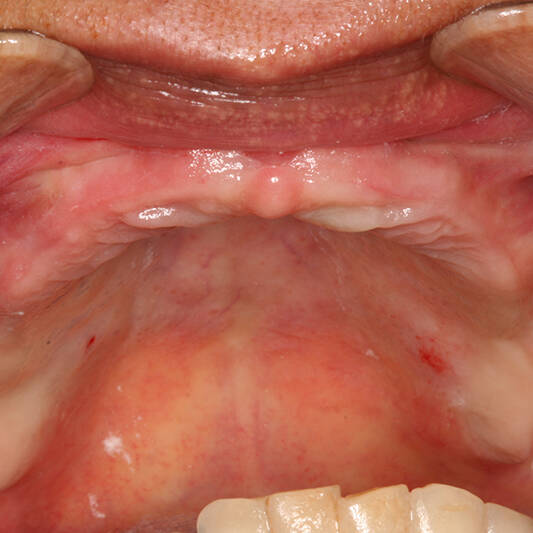

Na Clínica Pontes Odontologia, somos referência em implantes dentários em Fortaleza, oferecendo tratamentos de alta qualidade e tecnologia de ponta. Os implantes dentários são estruturas de titânio posicionadas cirurgicamente no osso maxilar ou mandibular para substituir as raízes dos dentes ausentes. Essa técnica permite a fixação de próteses personalizadas, restaurando a função mastigatória, a estética e a autoestima dos nossos pacientes.